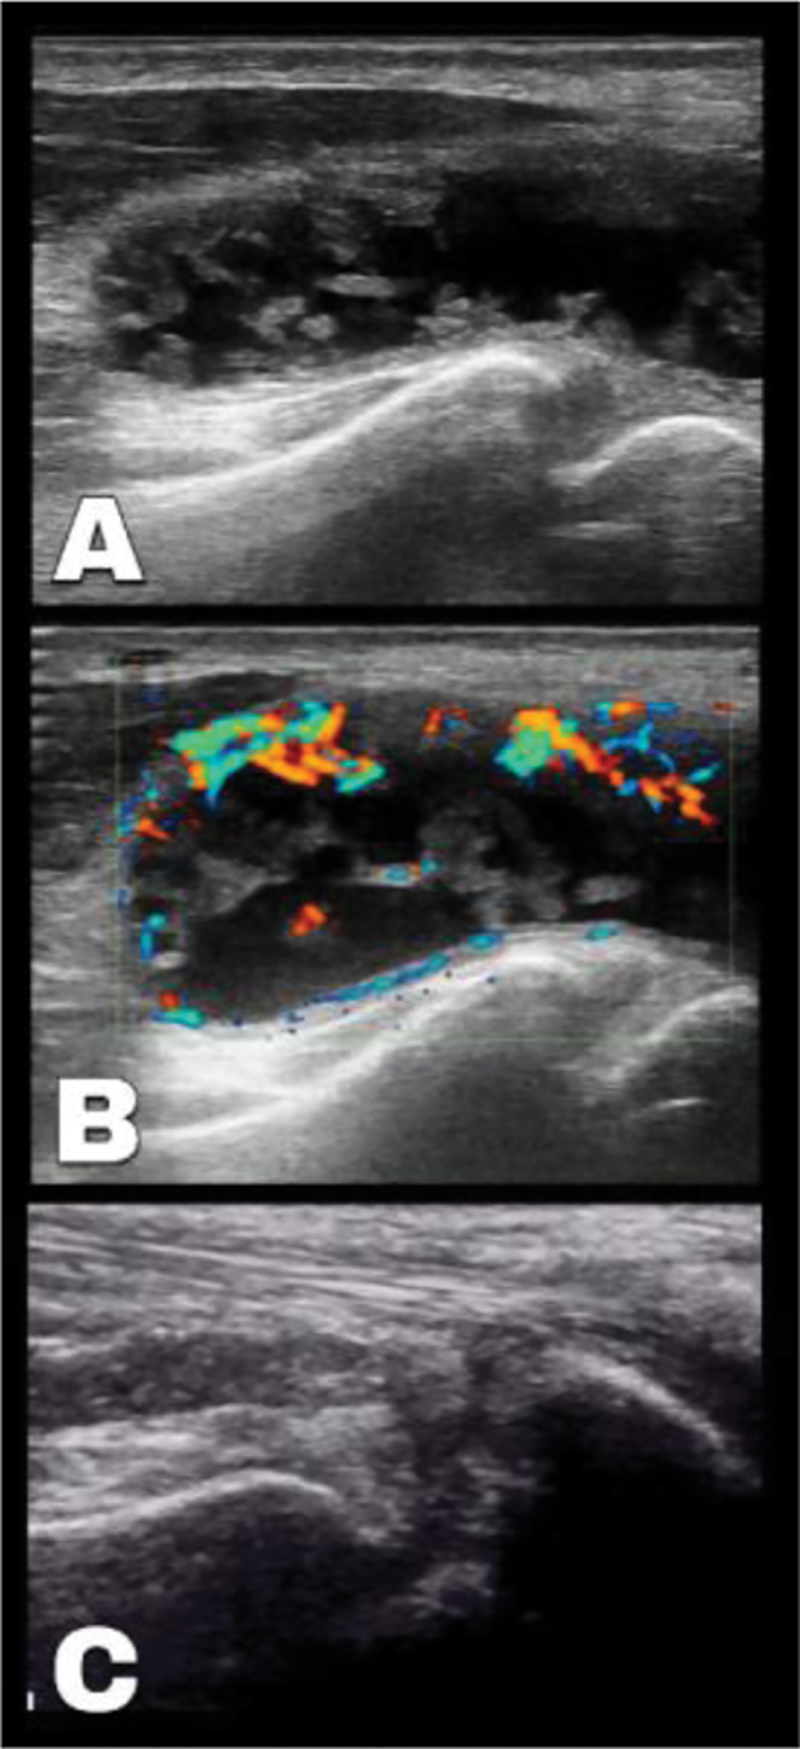

palmar longitudinal ultrasound scan over the radio-carpal region, A: Synovitis with effusion in the common flexor Sheath, B: Positive Color Doppler denoting active synovitis, C: Follow up ultrasound scan showing resolution of synovitis and effusion.

Methods: 31 Years old female with psoriatic arthritis in the form of symmetrical hand arthritis for the last 10 years, and extensive nail disease shows partial control under treatment with Methotrexate after failure of sulfasalazine. Her DAPSA score usually ranges between 16 to 18 with tender persistent fluctuating cystic swelling overlying her right palm extending proximally to the distal third of the forearm that becomes more tens on fingers flexion. Ultrasound examination shows hypoechoic distension of the right common flexor synovial sheath, that is partially compressible and partially displaceable with highly positive Doppler signals indicating active synovitis.

Results: April 2020, on regular follow up patient achieve DAPSA remission <4, with complete resolution of the right palm swelling and she reports complete recovery of her hand function which is maintained up to January 2022 in her last follow up visit. Follow up ultrasound scan shows normalization of the common flexor sheath with disappearance of the mixed picture of synovitis and effusion.